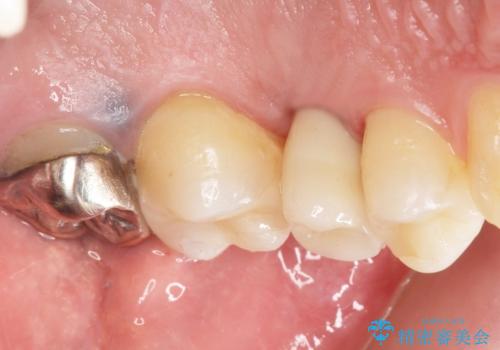

残根状態になっている左上の小臼歯(左上5)を精査したところ、う蝕が歯肉縁下まで進行しており保存不可能な状態でした。

患者様のご希望により、抜歯後インプラント治療を行いました。

骨の厚みが不足していたため、インプラントの埋入と同時にソケットリフト(上顎骨に骨を増やす手術)を行いました。